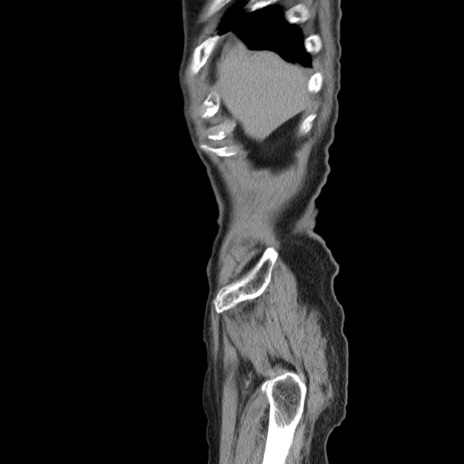

横断像

【症例】80歳代男性

【主訴】左側腹部痛、嘔吐

【現病歴】本日早朝より左腹部に痛みあり。昼頃嘔吐認めたため、救急要請。

【既往歴】直腸癌(Mile手術)、胆摘

【身体所見】意識清明、BT 35.9℃、BP 221/93mmHg、SpO2 97%(RA) 、腹部:左ストーマ周囲に限局性の腹部膨隆あり。 膨隆部自発痛・圧痛あり・軟。

【データ】WBC 7700、CRP 0.09